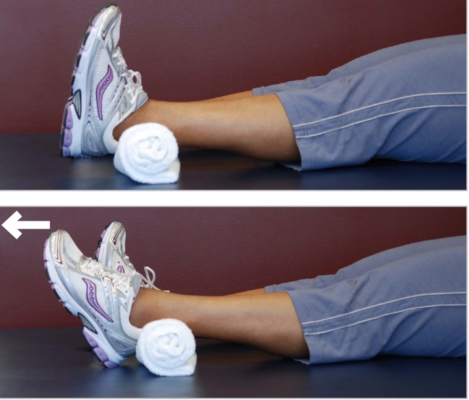

Các bài tập và Tập luyện chức năng

Mục đích cuối cùng của PHCN: tối ưu mức độ chức năng của bệnh nhân sau phẫu thuật.

Xin Xem phần 2.